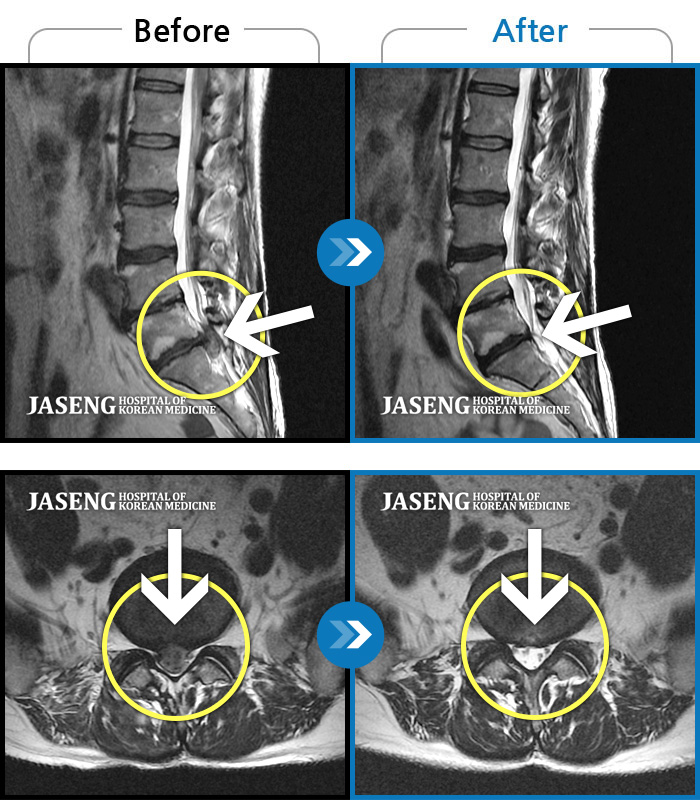

Before

After

환자에게 사전 동의를 받아 동일 조건에서 촬영되었습니다.

개인에 따라 치료 후 부작용이 발생할 수 있으니 의료진과 상담 후 치료를 진행하시기 바랍니다.